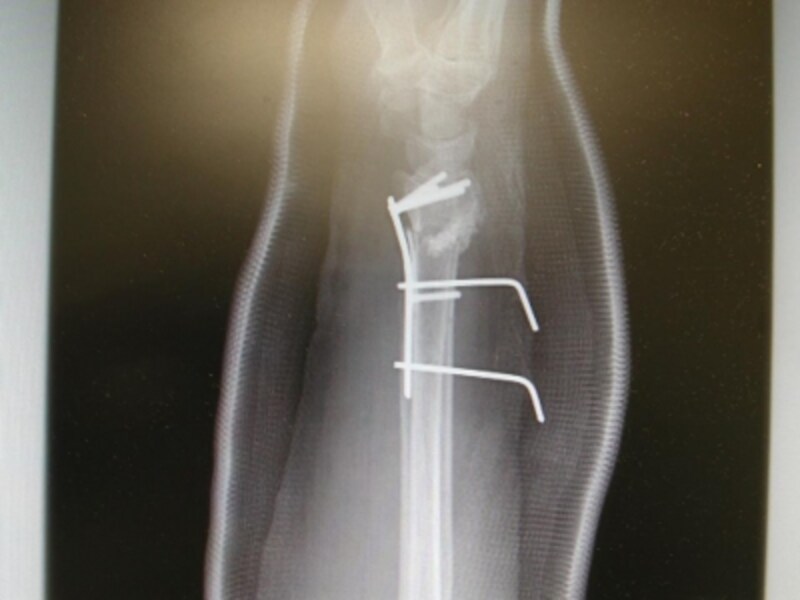

手術で橈骨を金属のプレートで固定しました。

側面像で骨片が良好な位置関係にあることがわかります。